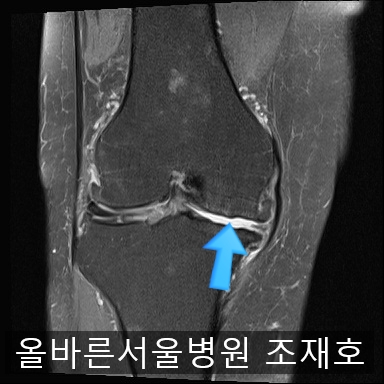

为了掌握具体情况拍了MRI。

内侧关节软骨几乎不见,软骨板也受损严重。软骨损伤部位充满关节液。

软骨板损伤严重